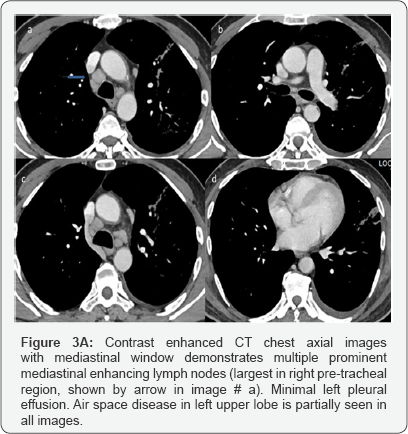

C. CT recommended to exclude underlying pathology /further evaluation considering patient age (Figure 3).

Impression: of Figure 3

CT with Contrast done after 4days of second X-ray chest.

Large area of consolidation seen involving left upper lobe with central area of ground glass opacity surrounded by rim of more density mainly at anterior aspect representing incomplete reversed halo sign.

Multiple prominent enhancing mediastinal lymph nodes. Minimal left pleural effusion. Right lung is clear.

In short term worsening and in view of history, likely community acquired pneumonia.

No mass.